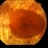

- retinitis pigmentosa, macula

- Tom Steele, CRA Midwesteye Institute, Indianapolis Indiana

- Imaging device

- Fundus camera

- 78-year-old male with advanced retinitis pigmentosa.